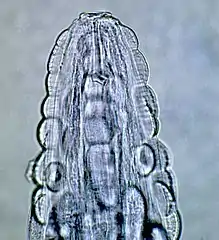

These are all pictures from a single Gongylonema pulchrum male extracted from a man in France.[1]

- Head

The morphology of the worm is as follows, from a 2000 Veterinary Medicine study: "The anterior end in both sexes was covered by numerous cuticular platelets. There was a pair of lateral cervical papillae. The buccal opening was small and extended in the dorsoventral direction. Around the mouth a cuticular elevation enclosed the labia, and eight papillae were located laterodorsally and lateroventrally. Two large lateral amphids were seen. On the lateral sides of the female's tail, phasmidal apertures were observed. The caudal end of the male was asymmetrically alate and bore 10 pairs of papillae and two phasmidal apertures."[3] The average length for male worms is 29.1 mm (1.15 in), while the average length for adult females is 58.7 mm (2.31 in). The worm is highly mobile, as observed in patients’ mouths and as evidenced by the morphological design of the worm.